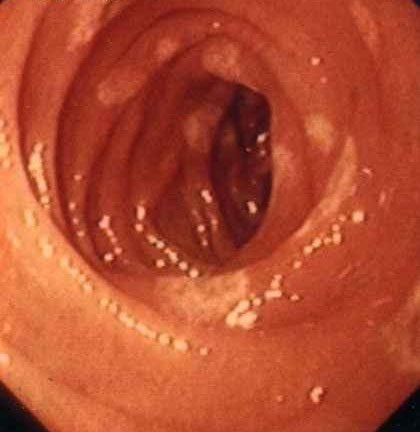

十二指肠炎的早期征兆

1.消化不良症状可有上腹饱胀、反酸、嗳气、恶心、呕吐等症状。部分患者可无症状及体征。

2.上腹痛,类似于十二指肠壶腹部溃疡,多为饥饿痛、夜间痛,进食后缓解。

3.上消化道出血是糜烂性十二指肠炎的一种并发症,可有黑便或呕血。

4.常见的体征有上腹部轻度压痛,部分患者可有舌炎、贫血和消瘦等。